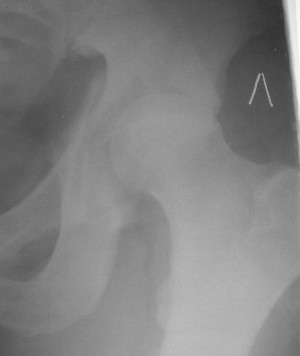

Привет! Вот недавно прооперировали похожий на ваш случай - впадина + шейка (правда у нас впадина поперечный+задний край). После травмы прошло 4 недели. мужчине 46 лет. С такой комбинацией все показания к первичному протезированию. Морально и технически мы к этому уже созрели.Но больной не собрал денег на протез. Выполнили остеосинтез впадины и шейки, прекрасно понимая, что головка вскоре рассосется, мы хотя бы надемся что к этому времени таз срастется, как говорится создали все условия для дальнейшего протезирования (может, и протез в последующем подешевле будет, в смысле, без укрепляющего кольца?). Привет Рункову!

Привет Алекей! Сделано неплохо, поздравляю, хотя второй винтик можно было бы и подлиннее в шейку загнать! Пара вопроов: доступ такой же? головка была свободной или висела на капсуле?

Согласен, можно было и подлиннее. Доступ такой же - чрезвертельный, только разрез кожи прямой (а не Y, чего то я разницы не ощущаю). Головка была абсолютно свободной (то есть во время остеосинтеза таза лежала в стакане и не мешалась). Шансов, что она прирастет 0,00001%. Хотели даже выбросить, но привинтили как временный биологический протез (читай свободный трансплантат), чтоб на период срастания таза бедро проксимально не ушло (может ортопеды потом спасибо скажут). Ну а у вас первичное протезирование при переломе впадины тоже пока полько в планах?